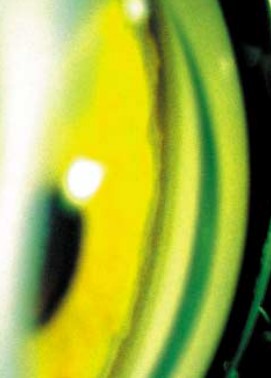

- Зрачковая зона радужки шире ресничной и выглядит как сероватое или желтое кольцо с ровной либо ватообразной поверхностью.

- Ресничная зона за счет обнажения пигментного листка имеет значительно более темный шоколадно-коричневый или сине-лиловый цвет.

- В прикорневой части ресничной зоны может отмечаться желтовато-оранжевого цвета недифференцированная губчатая мезодермальная ткань.

При этом зрачковый пояс ощутимо шире цилиарного. Дефектов пигментного листка биомикроскопически и диафаноскопически не обнаружено. Имеется легкая вытянутость зрачка по горизонтали в височную сторону с незначительным локальным утолщением пигментной каймы. Отмечается некоторая неравномерность ширины лимба, на фоне которого определяется частичный задний эмбриотоксон, наиболее четко выявившийся в дальнейшем после нормализации ВГД и исчезновения роговичного отека.

Левый глаз. Острота зрения OS=1,0. ВГД=18 мм рт.ст. Глаз спокоен. Роговица прозрачная. Имеется некоторая неравномерность ширины лимба, признаков заднего эмбриотоксона не отмечено. Передняя камера средней глубины, влага ее прозрачна. Радужка имеет двухцветную окраску, идентичную таковой правого глаза.